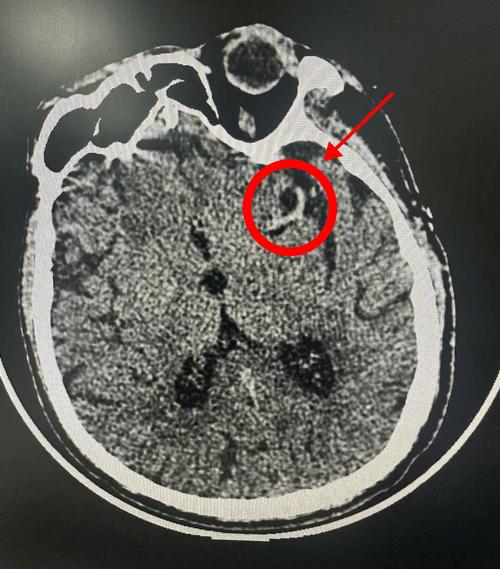

- 豆状核边缘模糊:这是一个非常经典的早期征象,正常情况下,大脑深部的“豆状核”结构边界非常清晰,当供应它的血管发生缺血时,这个边界会变得模糊不清。

- “右侧基底节区...低密度影”:发现了病灶,位置在右侧基底节区,这里是常见的脑梗好发部位(供应血管是大脑中动脉的深穿支)。